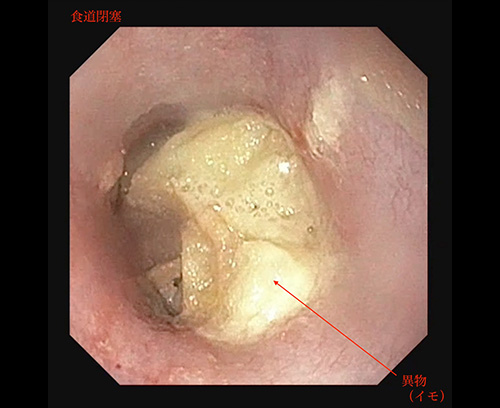

食道異物

食道異物による閉塞(おやつ)